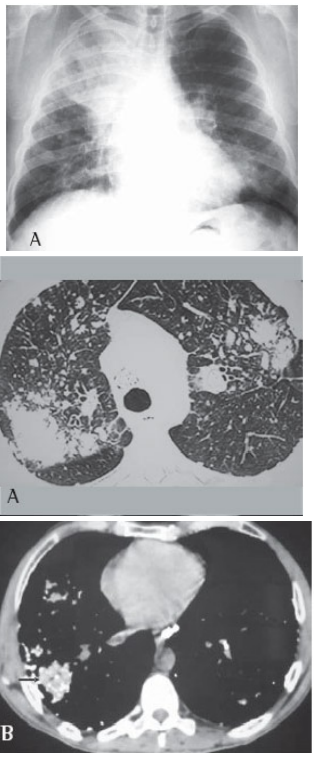

Paciente do sexo masculino, de 44 anos, trabalha há 20 anos em pedreira. Tabagista com uso de 30 maços/ano. Iniciou há cerca de seis meses dispneia progressiva até pequenos esforços, associado com astenia e perda de peso. Foi encaminhado para avaliação. Nega patologias prévias ou uso de medicações. Ao exame, apresenta em regular estado geral, dispneico, saturação periférica de oxigênio 88%, frequência cardíaca 102 BPM, frequência respiratória 25 IRM. Solicitado alguns exames, descritos a seguir: Espirometria:

Pré-broncodilatador: CVF 1,64(48%), VEF1 0,73(26%), VEF1/CVF 45%

Pós-broncodilatador: CVF 1,99(59%), VEF1 0,90 (33%), VEF1/CVF 45%